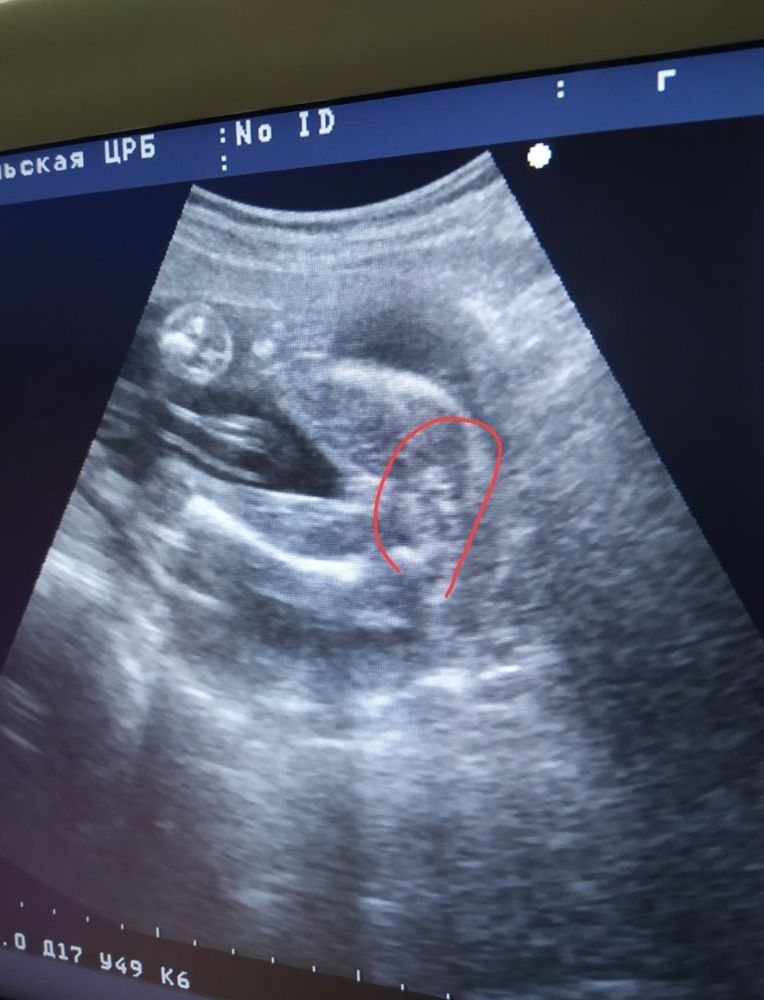

Фото УЗИ, пол ребёнка

Это попа у вашей дочи)

Это попа, а у вас девочка )

Гульнара Сабитова, ну да можно подумать что яички ) но это тень такая )

Узнать пол дубль 2 Кто же будет?!)